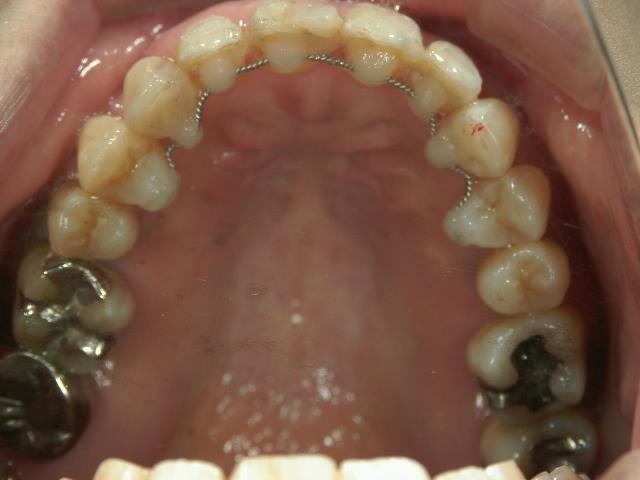

矯正歯科 治療前